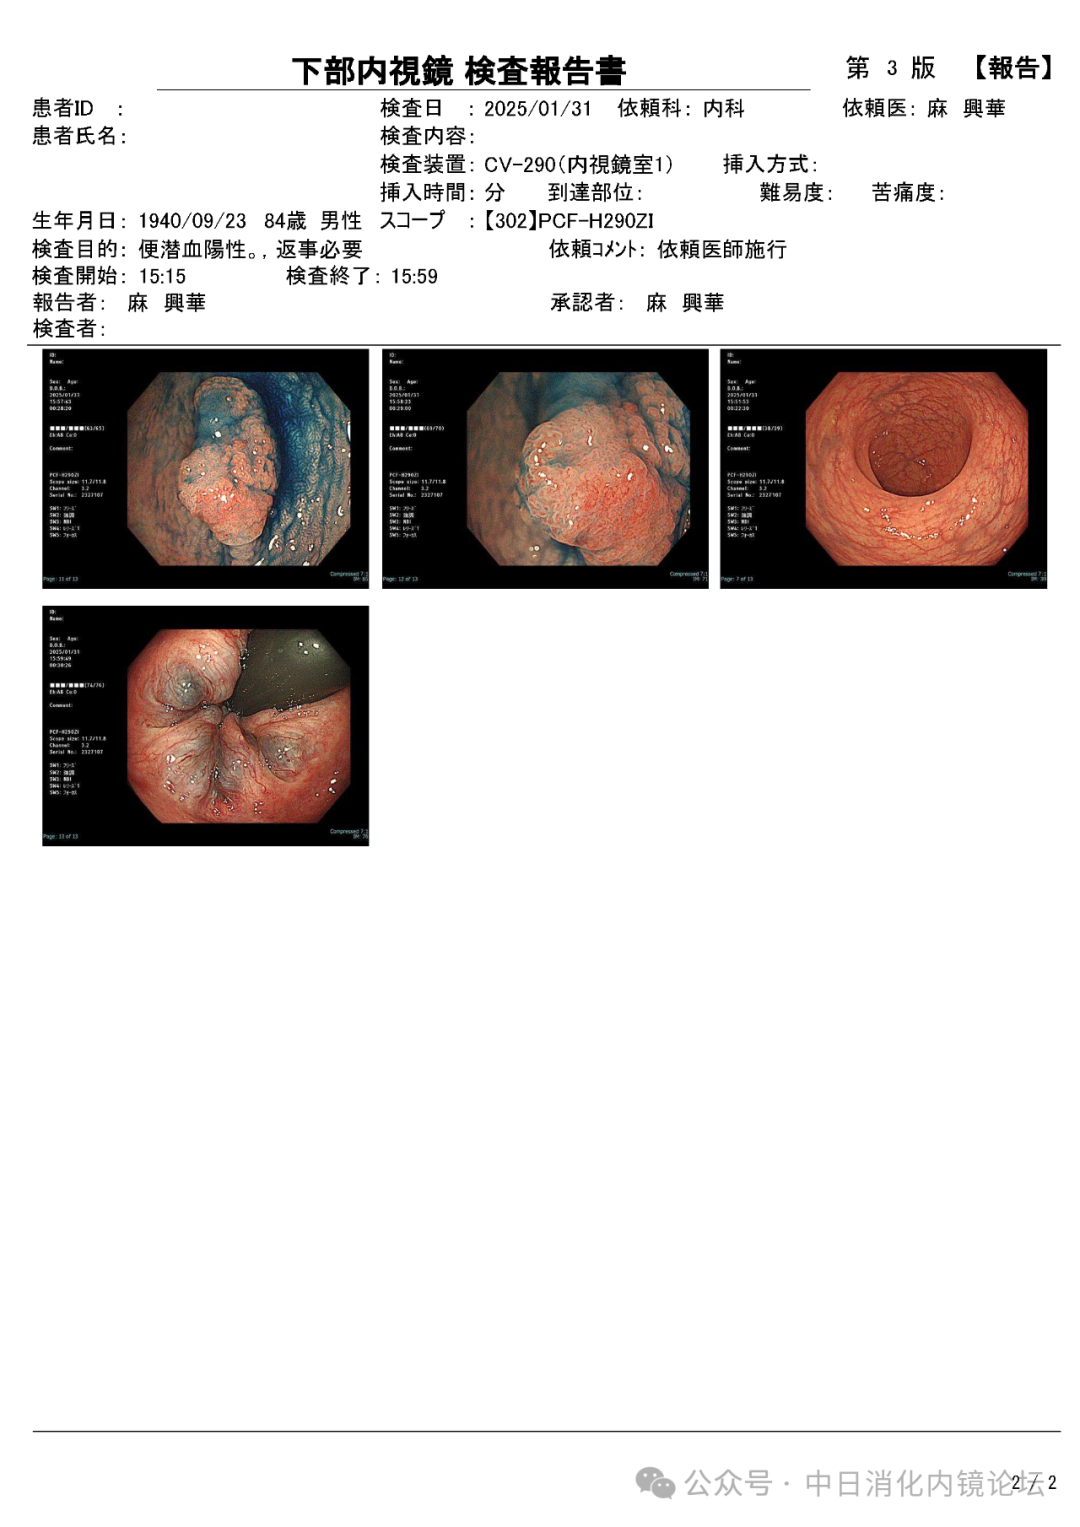

在繁忙的临床工作中按照日本消化内镜学会倡导的病变观察流程,便可事半功倍,极大地提高诊断准确性和检查效率。病变观察远景→近景→放大,白光→NBIJNET→靛胭脂 pit pattern。切除后创面确认,确保无残留,断端阴性→肛侧腹侧点墨标记→标本固定,为病理诊断以及今后可能的追加治疗提供完整精确的原始资料。